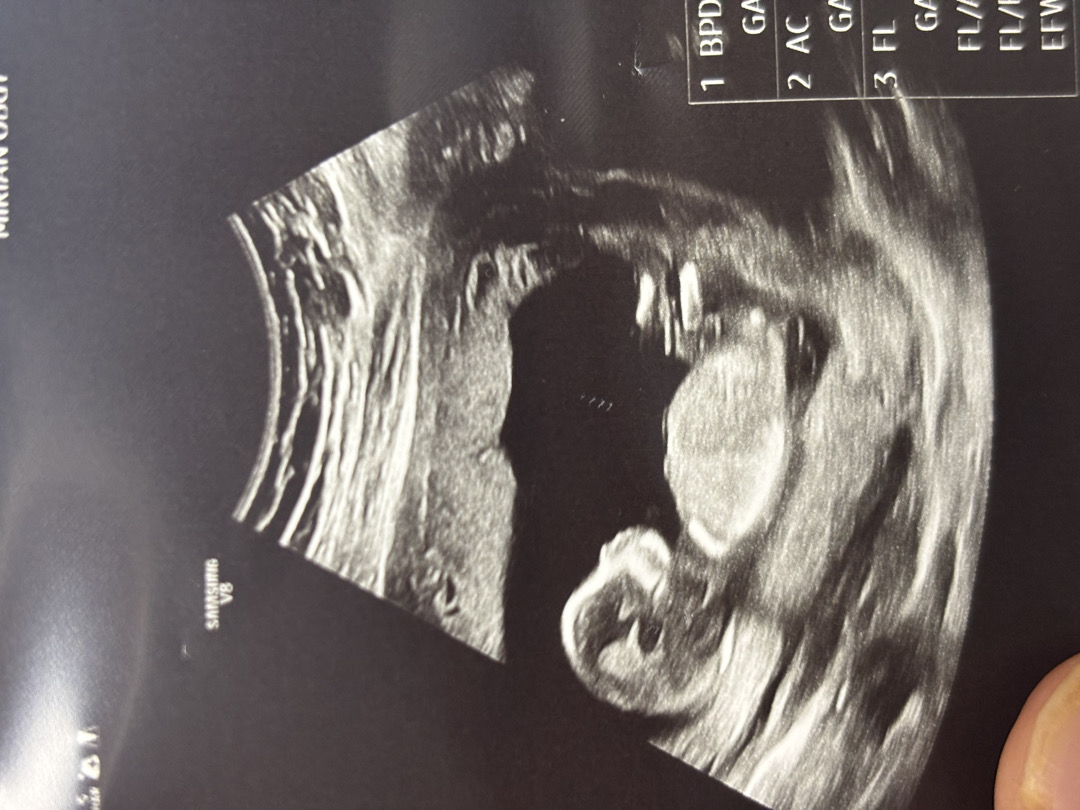

14주 5 일차 각도법 봐주실 천사분💖

병원에선 아직 성별 안알려주실거래요~~ ㅎㅎ 넘 궁금하네요 ㅠㅠ!!!! 뭘까요?!...